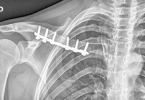

• 锁骨骨折内固定后多久可以活动

锁骨骨折内固定后多久可以活动

锁骨骨折内固定后一般需要4-6周开始逐步活动,具体时间需根据骨折愈合情况调整。锁骨骨折内固定术后活动时间受多种因素影响。骨折类型是重要因素,简单线性骨折通常4-5周可开始被动活动,粉碎性骨折可能需要5-6周。 ...